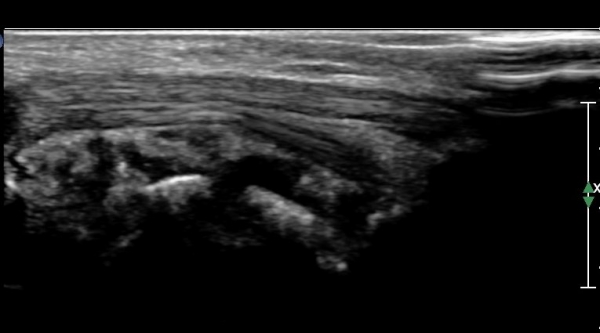

,¾ÆÅ³·¹½º°ÇÀ» âÀ¸·Î °üÂûÇÑ ¹ß¸ñ µÚ Á¾´Ü¸é°Ë»ç¿¡¼­ °Å°ñÇϰüÀýÀÇ ¼ö¾×Àú·ù°¡ °üÂûµÈ´Ù(»çÁø 7).